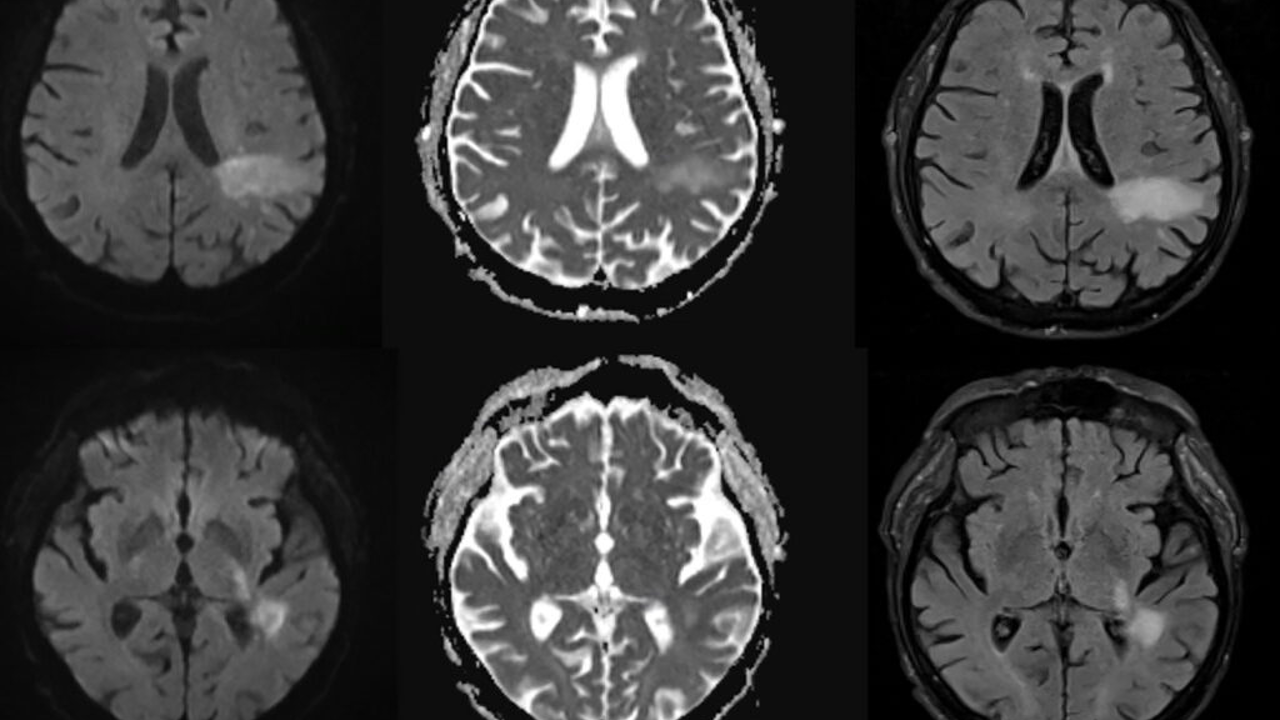

The human polyomavirus 2, or JC virus, is known as a silent killer virus that infects up to 90% of people and causes a disease called progressive multifocal leukoencephalopathy (PML), which can cause severe symptoms such as speech impairments, visual defects, motor dysfunction, and seizures. Researchers have found a new way for this virus to activate, potentially affecting up to 10% of adults worldwide. The JC virus invades the brain, destroying specific brain cells, leading to extensive demyelination and death.